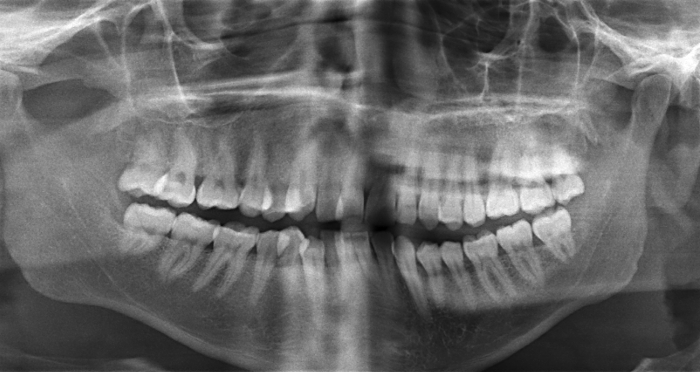

What is wrong with this image?

chin down

rami tipped in; OP very smiley